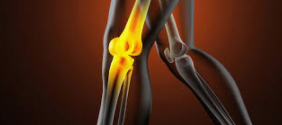

| 무릎 물참 치료 방법

대부분의 경우에는 2일~3일 정도 휴식을 취해 관절에 무리를 주지 않으면 자연 치유가 됩니다. 하지만 일상 생활에 불편함이 있거나 빠른 치료를 원하시는 분들은 관절에 물이 찬 위치에 주사기로 물을 빼는 시술과 소염제로 약물치료를 받습니다.

| 무릎 물참 주의 사항

무릎에 물을 주사기로 강제로 빼는 경우에 소염제 효과로 염증이 가라앉으면 물이 다시 차지는 않습니다. 하지만 염증이 사라지지 않고 물만 빼게 된다면 다시 물이 차게 되는 증상이 반복됩니다. 자주 주사기로 물을 빼는 시술을 받으면 주사기에 의해 조직손상이 발생될 수 있으므로 오히려 무릎 통증이 더 악화될 수 있습니다. 주사기로 물을 빼는 시술을 받기전 충분히 전문의와 상담 후 진행하시는게 좋습니다.